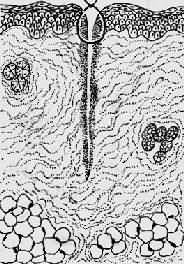

1.一般愈合(healing by first intention)见于组织缺损少、创缘整齐、无感染、经粘合或缝合后创面对合严密的伤口,例如手术切口。这种伤口中只有少量血凝块,炎症反应轻微,表皮再生在24~48小时内便可将伤口覆盖。肉芽组织在第三天就可从伤口边缘长出并很快将伤口填满,5~6天胶原纤维形成(此时可以拆线),约2~3周完全愈合,留下一条线状瘢痕。一期愈合的时间短,形成瘢痕少(图2-5)。

1.创缘整齐,组织破坏少

2.经缝合,创缘对合,炎症反应轻

3.表皮再生,少量肉芽组织从伤口缘长入

4.愈合后少量疤痕形成

图2-5 创伤一期愈合模式图